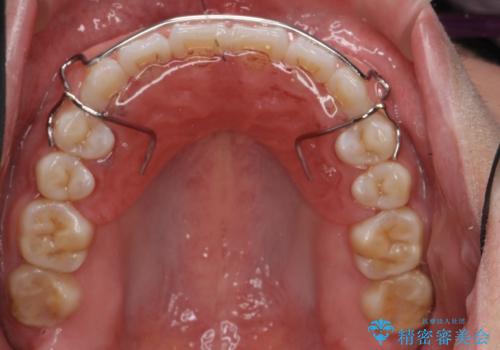

プレートタイプの保定装置について

当院では日中に使っていただく審美性に優れたマウスピースタイプの保定装置とは別に、プレートタイプの保定装置をお作りするすることもできます。

プレートタイプの保定装置は清掃性が高く、臼歯離開(上下の奥歯どうしに隙間ができる症状)等、咬み合わせの問題が生じにくいのが特徴です。